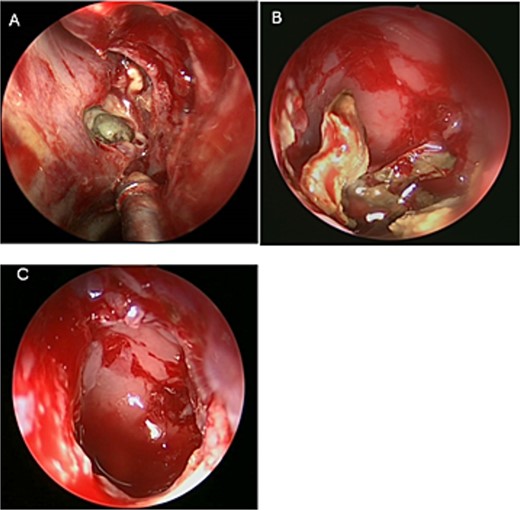

An asthmatic 42-years-old patient who was previously medically treated for allergic rhinitis with no significant improvement. A subsequent CT scan revealed isolated sphenoid sinus disease (Fig. 3). Intra-operative endoscopic findings revealed fungal mud and mucin (Fig. 4A and B) with post-operative (Fig. 4C) endoscopic finding of widely open, clean sphenoid sinus. Further histological examination of the specimen proved the diagnosis of eosinophilic AFS.

Intra-operative (a, b, and c) endoscopic sphenoidotomy showing mud and mucin, with post-operative examination (d) of right optico-carotid recess showing wide and clean sphenoid sinus.